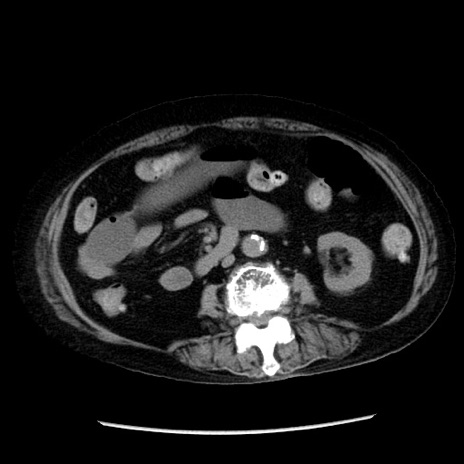

冠状断像

【症例】 90歳代女性

【主訴】 腹痛・嘔吐

【現病歴】今朝から左側腹部痛を認めた。 経過観察していたが、嘔吐を認めたため来院。

【既往歴】 子宮癌術後

【身体所見】 意識清明、BP 127/54mmHg、P 98bpm Sp02 95%(RA)、BT 35.8°C、腹部平坦・軟腸ぜん動音聴取良好、右下腹部圧痛(+) 反跳痛なし

【データ】WBC 9800、CRP 0.46